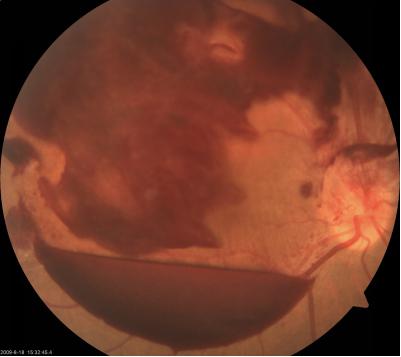

那什么是眼底出血呢?眼底出血是你自己看不到的,必須由眼科醫生借助眼底鏡或者眼底照相機等專業工具才能發現的出血。比如下圖: